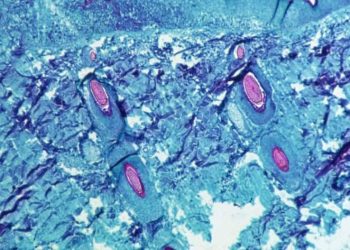

Read more১১ দেশে মাঙ্কিপক্স, বেশি রোগী জার্মানিতে

চট্টগ্রাম, ২১ মে, ২০২২: ইউরোপে ১০০ টিরও বেশি কেস নিশ্চিত বা সন্দেহজনক হওয়ার পরে বিশ্ব স্বাস্থ্য সংস্থা শুক্রবার মাঙ্কিপক্সের সাম্প্রতিক...